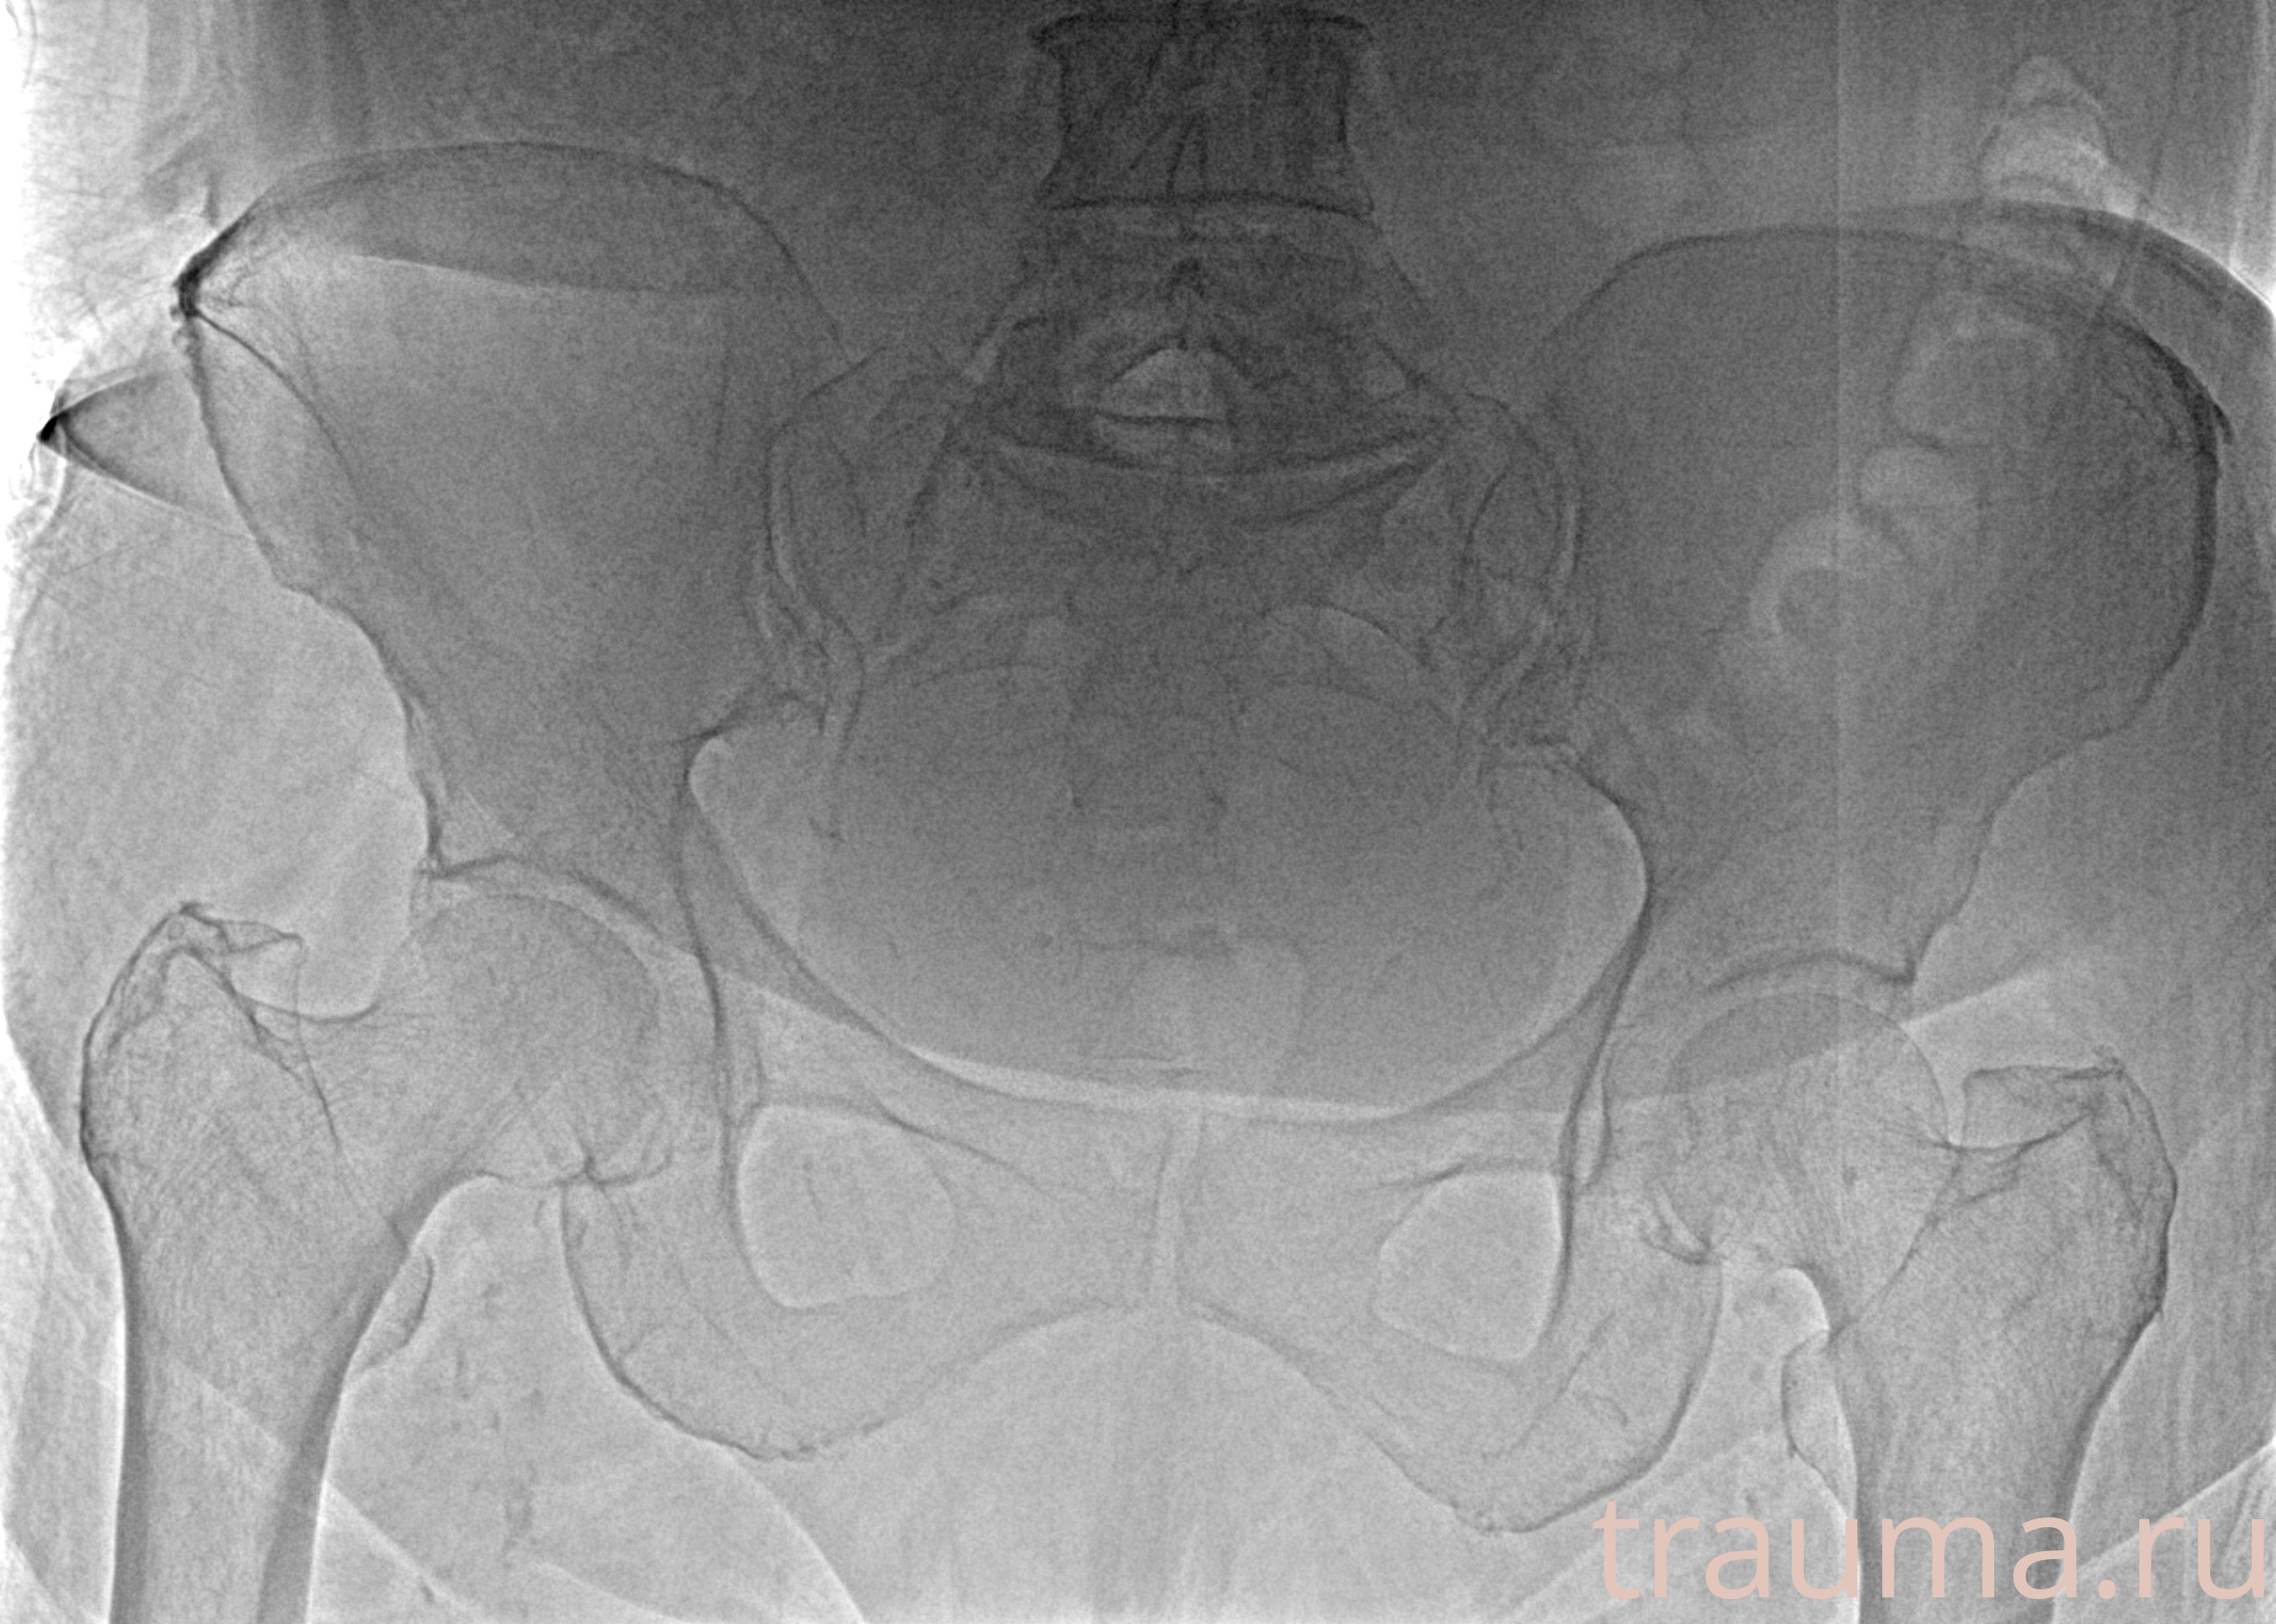

Рентгенограммы

Рентген на дому: по вашему адресу приезжает врач-рентгенолог, травматолог-ортопед с мобильным рентгеновским аппаратом, проводит диагностику травмы или заболевания, делает необходимые рентгенограммы, дает рекомендации по дальнейшему лечению. Получить качественные снимки в домашних условиях возможно благодаря уникальной методике, разработанной МосРентген Центром для института  Склифосовского